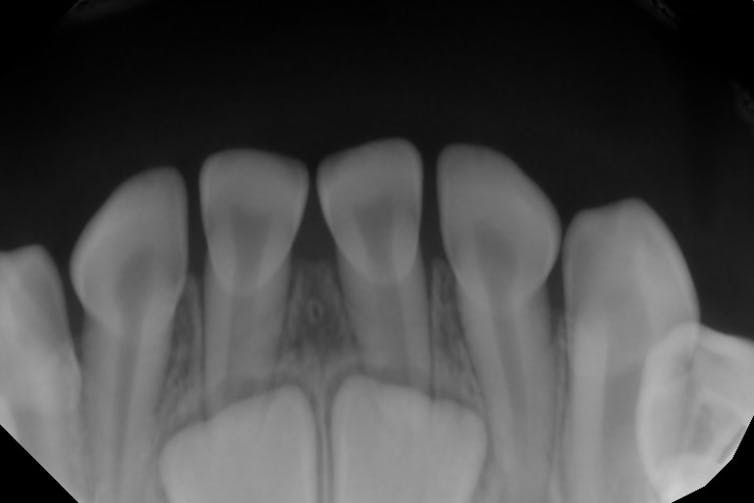

Most people are born with no teeth showing in their mouths at all, even though your baby teeth start developing before you’re even born. Baby teeth usually start poking through the gums when you’re between 6 and 8 months old. Sometimes when dentists take X-rays to check for cavities or other problems, they can see adult teeth growing within the gums.

David Avenetti

Baby teeth are relatively small because they need to fit in the small faces of babies and little kids. As you grow older and your face gets bigger, you have room in your mouth for more and larger teeth. Teeth have different sizes and shapes, depending on their purpose. Human front teeth are good at biting into things and tearing off a piece of food. Your back teeth are good at chewing foods into smaller bits before you swallow.